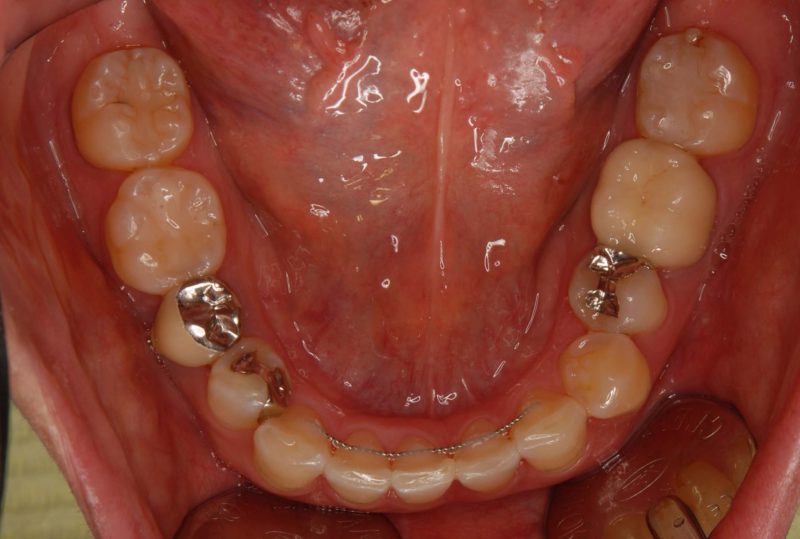

治療後: 歯並びが綺麗になり、思いっきり笑えるようになりました!

院長のコメント: 治療期間は9か月でした。部分的な矯正が、患者さんの悩みを解決するのにとても有効なことがあります。